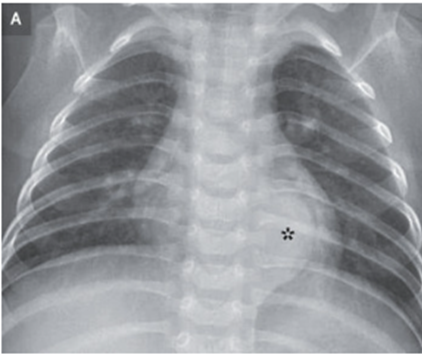

9歳男児。1年前から発疹と3ヵ月前からの腹痛と下痢を訴え小児科を受診した。 生後6か月の時点で原因不明の亜鉛欠乏症のため、以降経口Zn補給を受けている。 201…